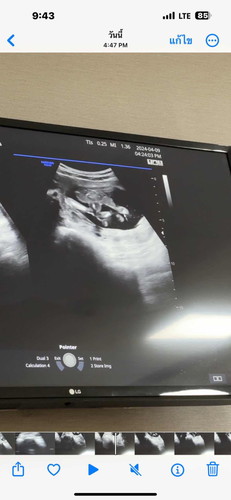

แม่คะรบกวนค่ะแบบนี้ลูกจะเป็นผู้ชายรึผู้หญิงคะ☺️🙏🙏

ภาพซาวด์แบบนี้ลูกผู้ชายรึผู้หญิงคะ